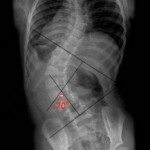

如果我有脊柱侧弯,我必须做手术吗?不。通常只有当曲线大于50度时才考虑手术。要么是这种情况严重影响了一个人的日常活动或他/她的生活质量。大多数脊柱侧弯病例不需要手术。只有在[…]